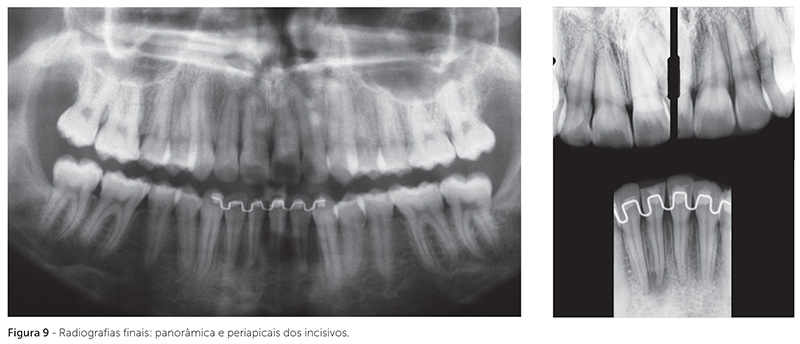

A radiografia panorâmica final mostra o paralelismo radicular obtido e, nas radiografias periapicais, pode-se visualizar a ausência de reabsorções radiculares (Fig. 9). Durante o tratamento, sugeriu-se aos pais que o dente 41 fosse restaurado. Contudo, o clínico odontológico geral solicitou que se aguardasse até o final do tratamento para realizar esse procedimento. Ao final, o dente 41 apresentou rarefação apical, conforme se observa na radiografia periapical final. A paciente foi indicada ao profissional competente para o tratamento endodôntico e restauração desse dente, os quais foram realizados um mês após a remoção da aparelhagem ortodôntic. Em controle radiográfico após seis meses, esse dente apresentava reparo periapical (Fig. 10).